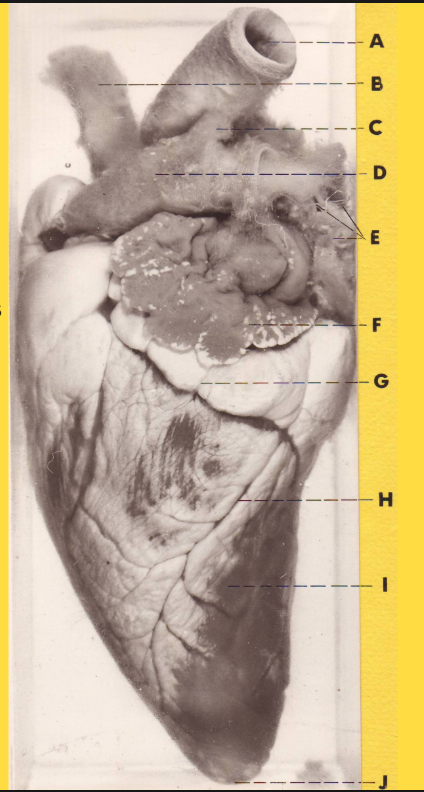

What is A?

right auricle

What is B?

brachiocephalic trunk

What is C?

left subclavian artery

What is D?

Aorta

What is E?

ligamentum arteriosum

What is F?

pulmonary trunk

What is G?

left auricle

What is H?

Great cardiac vein

What is I?

Left ventricle

What is J

Apex